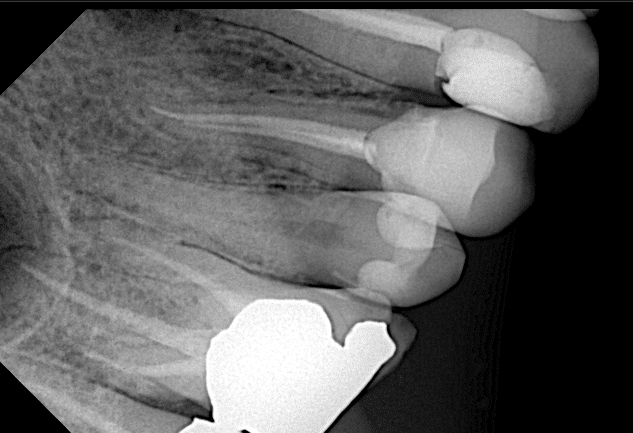

Firstly during trying the restoration I take x ray and see the overhang so I returned it to the lab to correct the overhang

Now the fitness is good

And this after cementation

Beautiful fitness like one piece